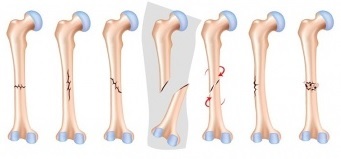

Definitions of…